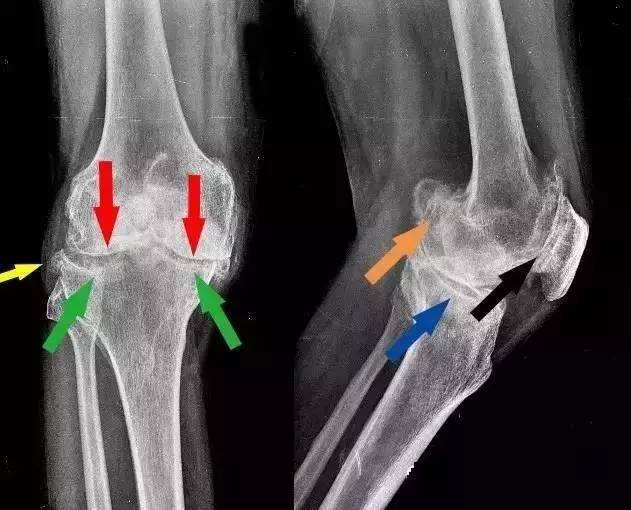

甭管是什么原因引起的,长出来的“骨刺”本质上依旧是骨骼。也就是说,新长出来的骨刺和全身其他部位的骨头,并没有任何成分上的区别。不仅外观上无区别,在片子上无区别,甚至连成分都一样。